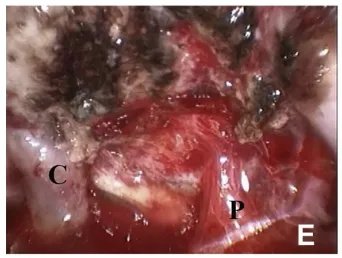

▼(E)30度内窥镜检查显示左侧颈内动脉(C)和垂体柄(P),显微镜下未见。

▼(C)经眉切口眶上入路。

这台手术由INC国际神经外科医生集团旗下国际神经外科顾问团的德国Henry W.S.Schroeder教授亲自操刀,Schroeder教授作为德国以及国际神经内镜专家,在国际神经外科学界享有盛名。他经常作为特邀讲师指导国内神经外科专家开展垂体瘤、脑膜瘤等神经内镜手术技术培训,普及神经内镜手术在国内的应用,与国内神经外科专家共同交流进步。Schroeder教授还和德国其他教授一起合著、编纂了《神经内镜手术》一书。在神经内镜设备领域出名的小儿神经内镜Lotta内镜就是Schroeder教授在2004年发明。